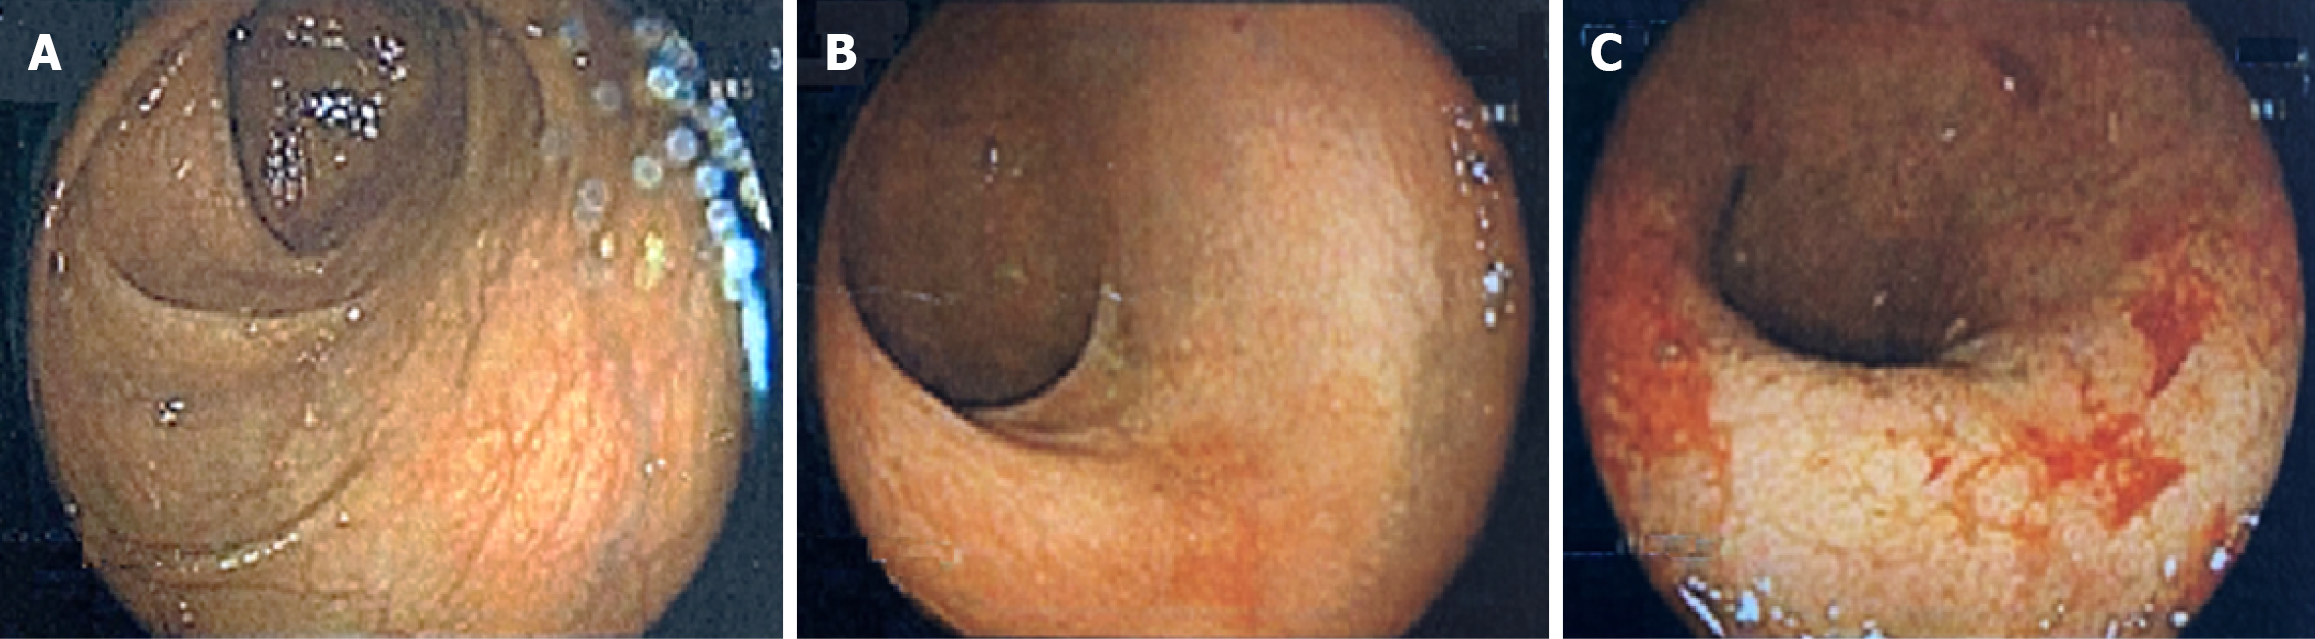

Figure 1 Colonoscopy images (colonoscopy performed at age 40 while managing ulcerative colitis with only oral corticosteroids).

A: Proximal left colon with normal vascular pattern and no mucosal lesions; B: Sigmoid colon with erythema and mucosal friability; C: Rectum with erythema, mucosal friability, erosions, and ulceration.